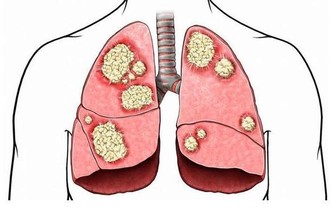

槐葉性微涼,可以清熱涼血、止血,還含有一種芸香甙類黃酮,能降低擴張毛細血管的總量,

保持毛細血管正常的抵抗力,恢復血管正常的彈性,減低通透性而達到止血作用。

因此,可以治療大腸火盛或濕熱蘊結導致的大便出血、痔瘡出血以及血淋等病症,而且效果極好。